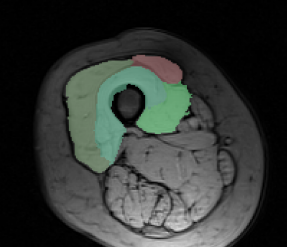

Dataset. The dataset consists of 30 MRI volumes of the thigh region of dimensions . The various segments correspond to 4 different muscle groups together with the background class. We randomly split the dataset into 80% for training and 20% for testing. In order to reduce the training time for both our method and the baselines, we divide each volume into volumes of dimension .

Results. Fig. 1 shows the test loss for three different methods: (i) the initial hand-tuned parameters ; (ii) the baseline structured SVM with distance transforms; and (iii) our proposed approach using latent SVM. As can be seen from Fig. 1, latent SVM provides significantly better results than the baselines—even when using the distance transform. For the 4 x 5 hyperparameter settings that we report (that is, four different values of and 5 different values of ), latent SVM is significantly better than SVM in 15 cases, and significantly worse in only 2 cases. Note that latent SVM provides the best results for very small values of , which indicates that the upper bound on the empirical risk in tight. As expected, for sufficiently large values of , all the methods provide similar results. For the best settings of the corresponding hyperparameters, the percentage of incorrectly labeled voxels as follows: (i) for , ; (ii) for structured SVM, ; and (iii) for latent SVM, . Fig. 2 shows some example segmentations for the various methods.